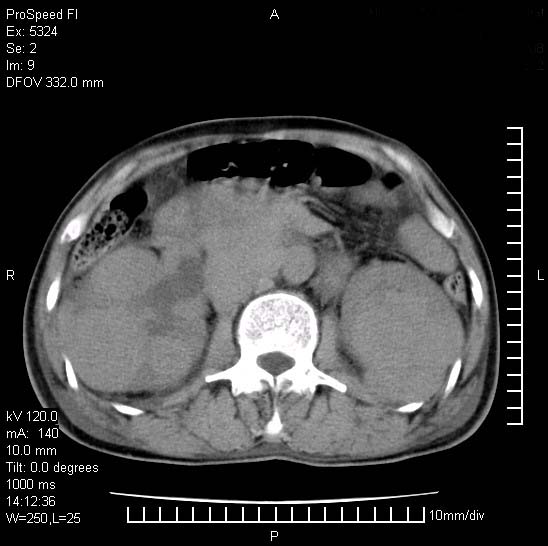

患者阴囊肿大14月,腰痛2个月,咳嗽,咳痰1周,患者现在肾功异常,做增强有些担心,我们用的是欧乃派克.

右侧肾癌伴腹膜后淋巴结转移!

右侧肾癌后腹膜转移,腹腔少量积液

腹膜后淋巴结肿大包饶腔静脉,双肾病变,建议增强

双肾均有软组织密度舯物,腹膜后淋巴结肿大包饶腔静脉------考虑为恶性占位病变,转移瘤可能。

1)考虑双肾恶性肿瘤(肾癌?)。2)腹膜后淋巴结肿大,多为肿瘤转移所致。

腹腔积液,双肾均有稍高密度肿块,主动脉旁广泛淋巴结肿大,融合,无显著肿块坏死征像,多考虑淋巴瘤累及双肾,不排除肾癌伴转移(肾癌这么大应该较多坏死了),另阴囊肿大,不知是实质肿大还是阴囊积液,如是是积液,多为腹腔肿块压近睾丸静脉所致,如是是实性的,多为淋巴瘤

1、淋巴瘤,双肾转移瘤;2、双侧肾癌,伴有腹膜后淋巴结转移。

双肾均有软组织肿块伴腹膜后淋巴结肿大融合,右侧结肠旁沟积液;考虑恶性肿瘤。转移瘤?淋巴瘤?

双肾增大,腹膜后多发肿大淋巴结影.首先考虑淋巴瘤.